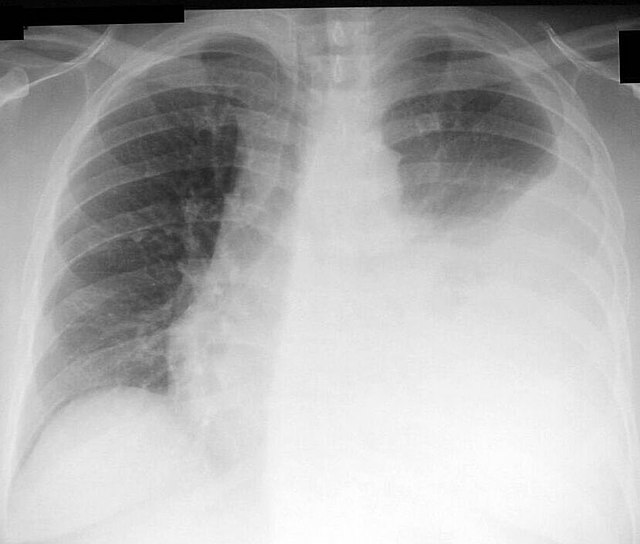

أنواع ثقب الرئة.. يرغب بعض الأشخاص في معرفة أنواع ثقب الرئة، لاسيما الذين يعانون من الإصابة بثقب الرئة أو ذويهم، والذي يطلق عليه أيضًا الاسترواحِ الصدري أو يعرف كذلك بالصدر المثقوب أو انخماص الرئة، وهو من الحالات الصحية الخطيرة التي تستوجب العلاج العاجل، فهيا نتعرف خلال السطور القادمة على أنواع ثقب الرئة.

وعن أنواع ثقب الرئة فحسبما ورد بموقع" ويب طب" يشتمل مرض ثقب الرئة أو الاسترواح الصدري على نوعين أساسين وهما على النحو التالي:

يدل توتر استرواح الصدر على وجود هواء متراكم تحت الضغط عادة ما يتسبب في انهيار إحدى الرئتين أو كلتاهما، ما يسفر عن وجود اختلال وظيفي حاد بالجهاز القلبي الوعائي.

فضلًا عن أن هذا الضغط المتراكم ينجم عنه بعض المشكلات الصحية، كبطيء أو إيقاف عودة الدم إلى الأوردة من القلب.

استرواح الصدر البسيط

وقد ينتج عن استرواح الصدر البسيط حدوث انهيارًٍا جزئيًا بالرئة مع ظهور أعراض ثقب الرئة؛ إذ أن الضغط الذي يتراكم بالتجويف لم يكن كافيًا لينتج عنه بعض المشكلات والاختلالات في وظائف القلب والأوعية الدموية.

ومع ذلك يمكن أن يتسبب في نقص مستويات الأكسجين بالدم، ما يسفر عن الإصابة بضيق التنفس.